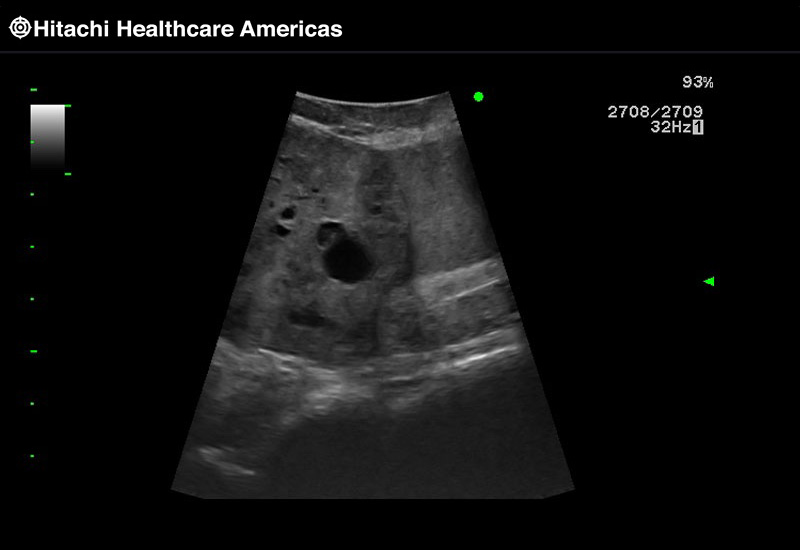

Superior guidance for all applications

Fujifilm Healthcare Americas is committed to designing tools that help surgeons navigate inside the human body and provide the necessary information to immediately make critical surgical decisions.

Fujifilm Healthcare's dedication to Surgeons provides outstanding ultrasound technology, professional support and the specialized tools necessary to best perform comprehensive real-time ultrasound imaging in Breast Surgery, General Surgery, Laparoscopic Surgery, Neurosurgery, Robotic Surgery and Surgical Oncology.

A critical function of robotic ultrasound guidance is tumor margin identification. Fujifilm's family of robotic probes all have the optimum location of the attaching mechanism that allows for full wrist articulation of the probe. The result is an increased confidence that the tumor margins have been completely identified.

Imaging Clearly Defined

State-of-the-art digital architecture and advanced imaging features to redefine the capabilities of surgical ultrasound.